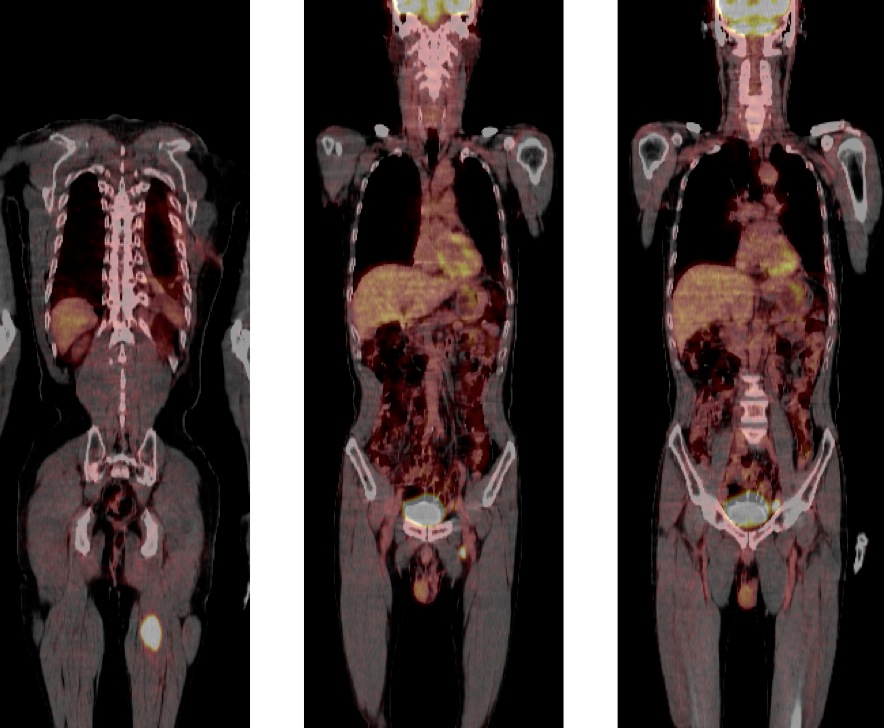

Figure 1 for case Adenocarcinoma lung metastasis

Figure 1